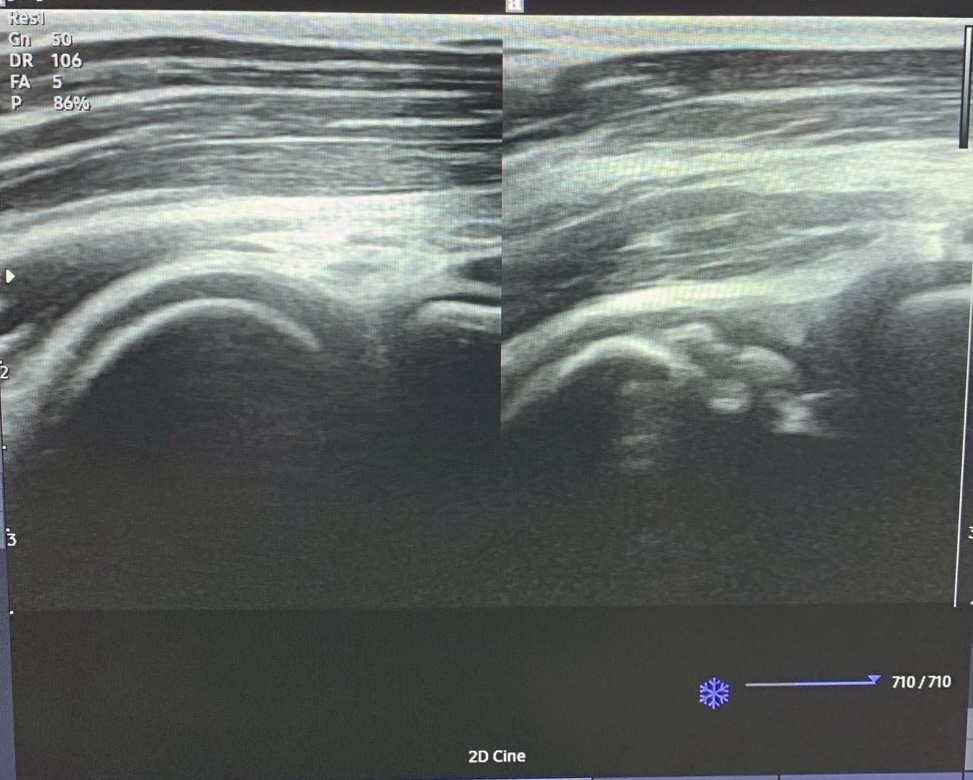

上記のエコー画像をご覧ください。

左側は症状の出ていない正常な状態で、骨の輪郭がきれいな丸みを描いています。

それに対して右側は骨の表面が崩れているように見え、関節面の不整が確認できます。

このような状態が認められた場合は

速やかに病院での精密検査が必要となります